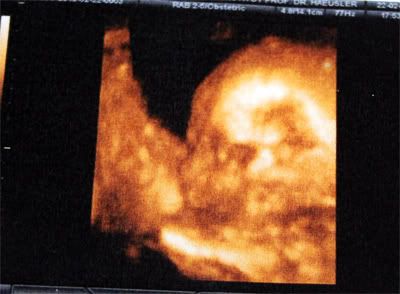

Nachdem ja einige von euch nachgefragt hatten, wollte ich mal unseren 2. Nachwuchs vorstellen 🙂

Seit gestern wissen wir, dass wir noch eine Tochter bekommen *freu*

Es war der Herzenswunsch unserer Großen, eine kleine Schwester zu bekommen und sie hat sich tierisch drüber gefreut.

Momentan wiegt die Zwergin 540gramm und ist ca. 29cm lang. Fusssohlenlänge 4,7cm 😉

Und hier noch ein 3D Ultraschallbild von ihrem Profil: